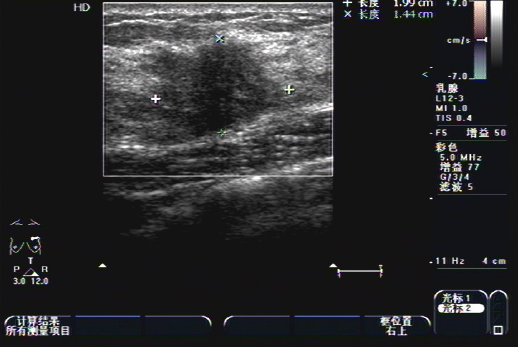

B超发现了我左乳中可疑的结节 | 作者供图